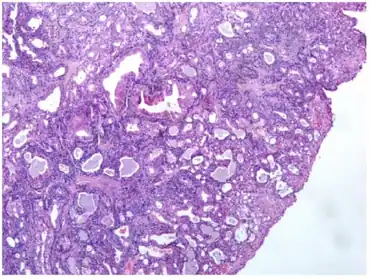

| Tumor is made of tubular and cystic structures | |

All of the tumors are unencapsulated, but are usually well defined or circumscribed. The overlying surface epithelium is not involved. The tumor shows a dual or biphasic appearance, with glandular or cystic spaces showing inner luminal secretory cells with abundant granular, eosinophilic cytoplasm subtended by basal, myoepithelial cells at the periphery, adjacent to the basement membrane. The luminal cells will often have decapitation (apocrine) secretions and will also have yellow-brown, ceroid, lipofuscin-like (cerumen) pigment granules. There is no pleomorphic, limited mitoses, and no necrosis.[2]